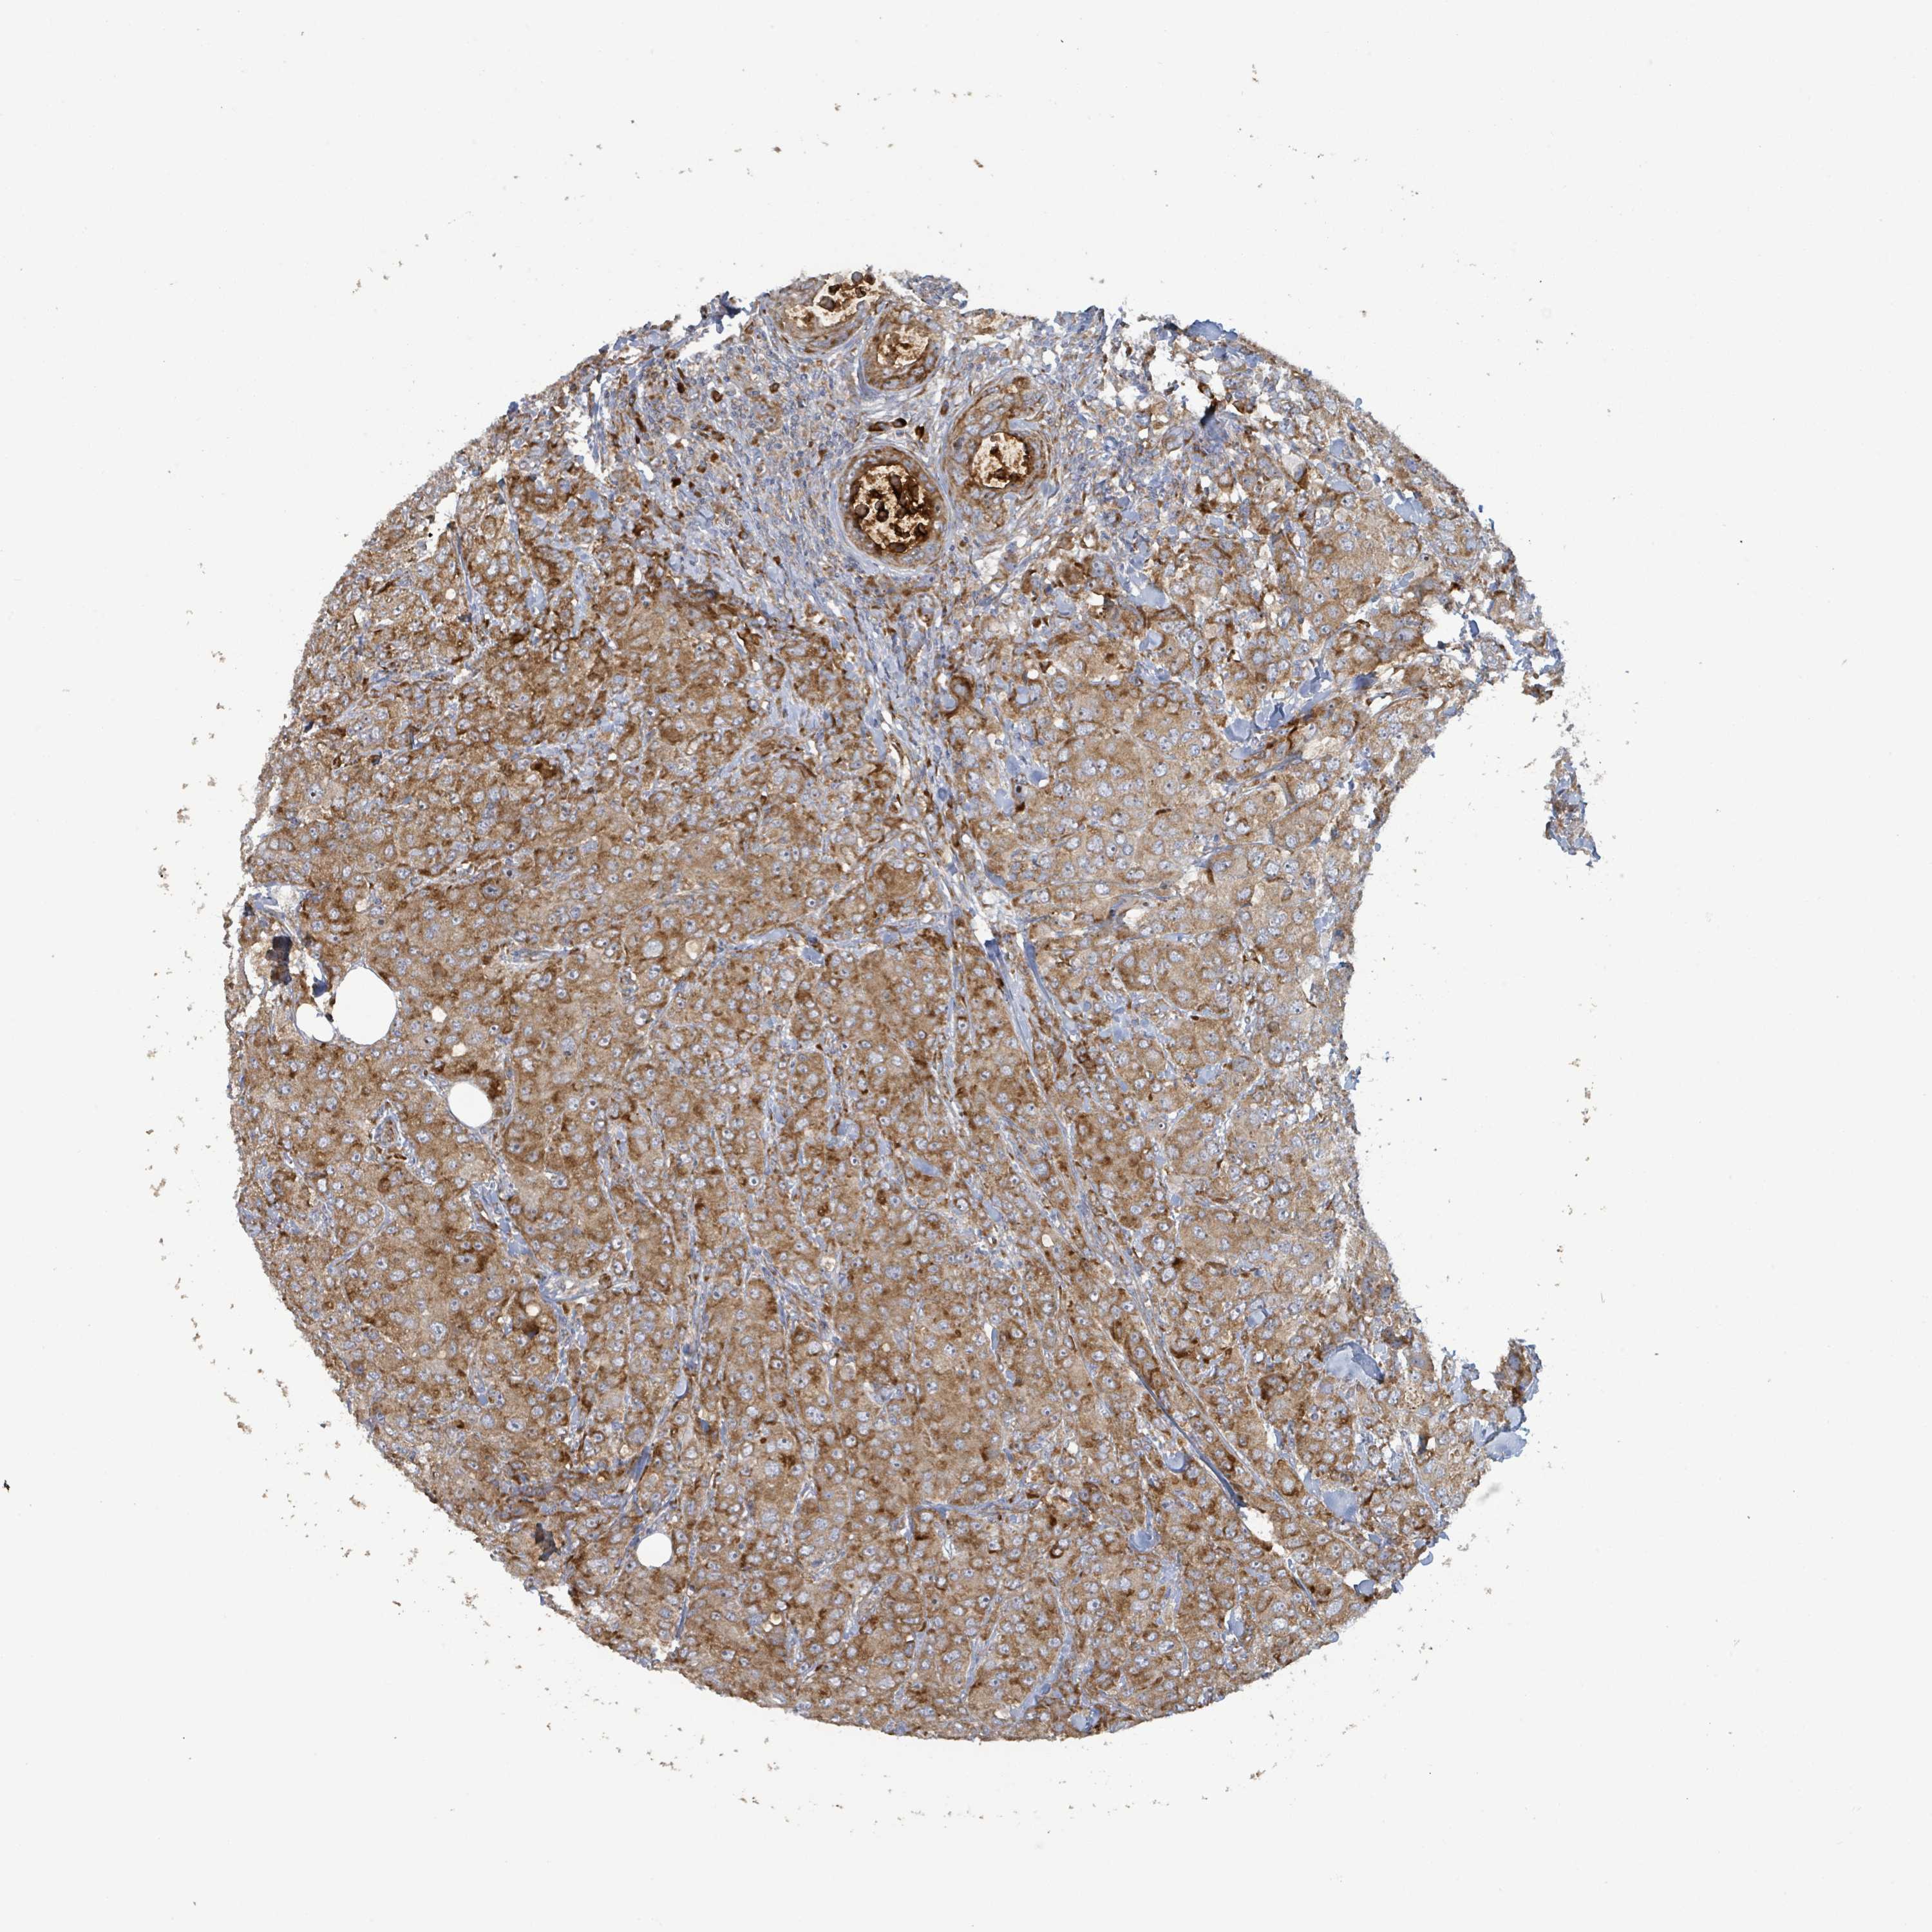

BRCA TCGA BRCA VALIDATION PROTEIN EXPRESSION